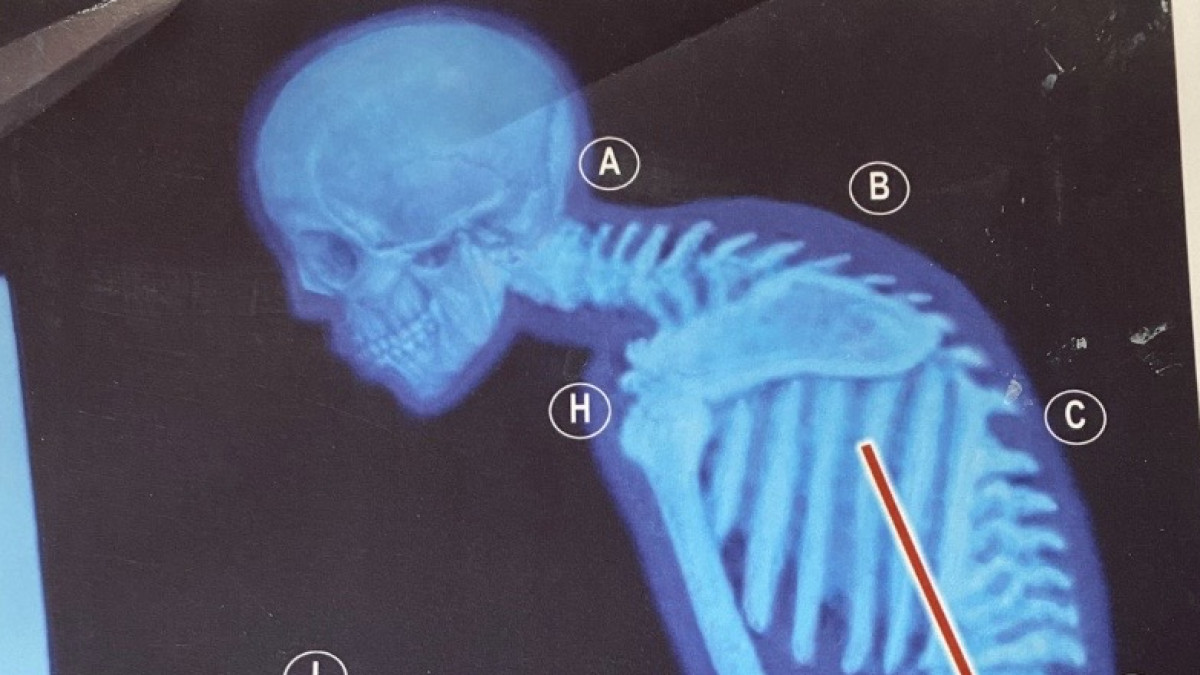

There is more than meets the eye when it comes to poor posture. Rounded shoulders, pot belly, tech neck, misaligned pelvis, sway back, and leg misalignment are the visible signs.

In this forward head posture, all the muscles responsible for tilting the head down become contracted. Since the head weighs about 11 or 12 pounds, the center of gravity changes, and the back muscles come into play to prevent falling over. This misalignment causes our bodies to compensate with sway backs, more profound curves, or even contracted abdominal muscles that cause a flat back.

Slouching creates excess pressure on the thoracic cavity leading to high BP and digestive issues - the compression makes digestion and elimination more difficult. Instead of checking off digestive problems to aging, they often correlate with poor posture. Slouching also causes shallow breathing (try it), making it difficult for the diaphragm to contract down. This breathing also signals panic and anxiety that release cortisol.